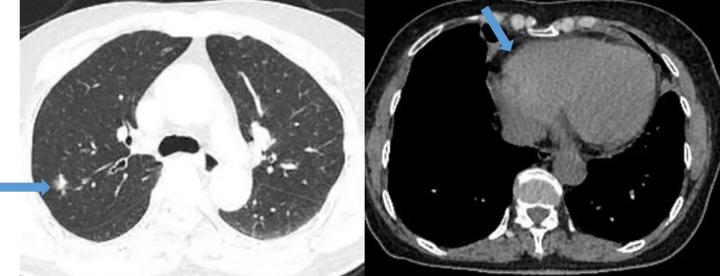

患者肺部CT结果,箭头(左)示肺部结节,箭头(右)示微量心包积液

颞骨薄扫CT,箭头(左、右上)示上颌窦炎症,箭头(右下)示双侧中耳乳突炎